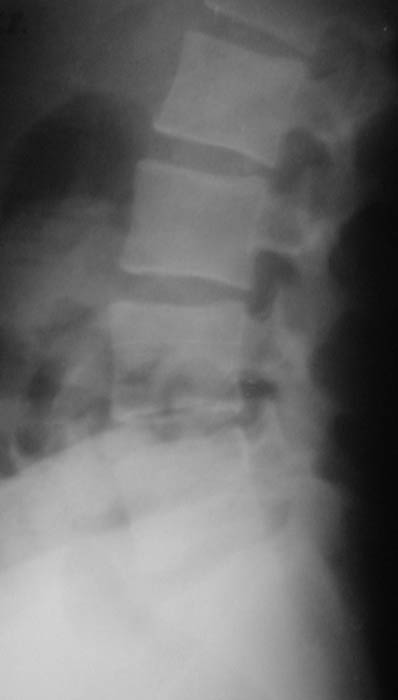

Уважаемые коллеги! Окажите, пожалуйста, консультативную помощь. Мужчина, 24 года. Туберкулез крестцово-подвздошного сочленения справа,

активная фаза. Болен в течение 6 месяцев. Проходил курсы НПВС - без эффекта. Жалобы на постоянные боли в поясничной области. Местно: крестцовая область припухшая, кожа не изменена, при пальпации боль, осевая нагрузка - боль, хромота на правую ногу. Общие анализы - без особенностей. МРТ 09.11.03. - патологических изменений в поясничном отделе не выявлено. Описание рентгенолога: остеосклероз, нечеткость контуров, участки деструкции в правом крестцово-подвздошном сочленении. Положительный анализ на антитела к микобактериям (IgM+E) от 16.10.03. Вопросы: уточнение диагноза, определение тактики лечения. С уважением, А.В.Владзимирский Донецкий НИИ травматологии и ортопедии Донецк, Украина